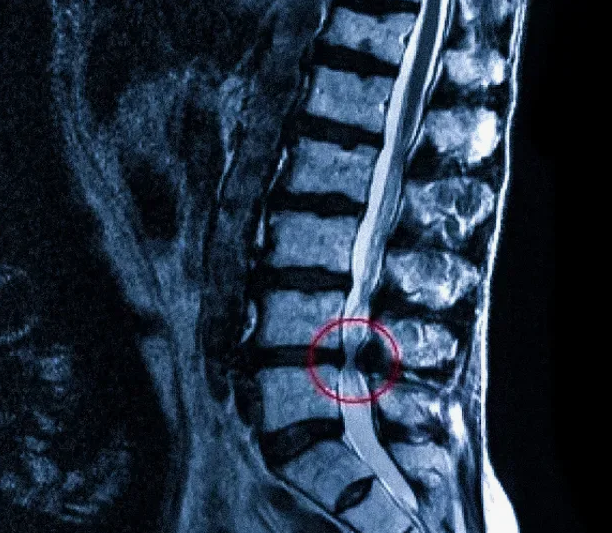

Магнитно-резонансная томография (МРТ):один из самых эффективных методов диагностики заболеваний